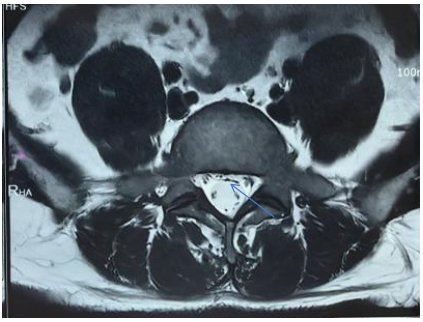

上述试验均检查神经受压情况,上述情况阳性说明神经受压明显,最终建议通过腰椎MRI确诊为腰4-5、腰5-骶1椎间盘突出并脱出,神经严重受压

以下是正常的椎间盘形态